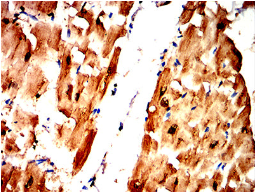

TNNT2 Mouse Monoclonal antibody[4B1D5]

The protein encoded by this gene is the tropomyosin-binding subunit of the troponin complex, which is located on the thin filament of striated muscles and regulates muscle contraction in response to alterations in intracellular calcium ion concentration. Mutations in this gene have been associated with familial hypertrophic cardiomyopathy as well as with dilated cardiomyopathy. Transcripts for this gene undergo alternative splicing that results in many tissue-specific isoforms, however, the full-length nature of some of these variants has not yet been determined.

Immunogen:    Purified recombinant fragment of human TNNT2 (AA: 1-295) expressed in E. Coli.

IHC    1/200 - 1/1000